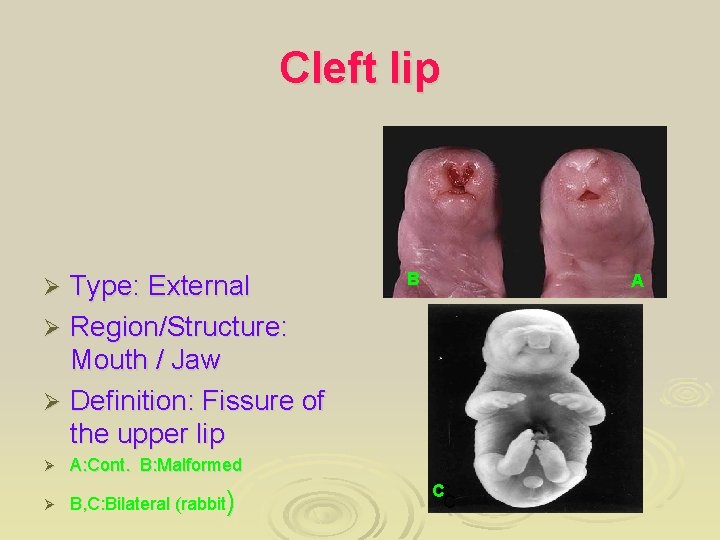

Cleft lip Type: External Ø Region/Structure: Mouth / Jaw Ø Definition: Fissure of the upper lip Ø Ø A: Cont. B: Malformed Ø B, C: Bilateral (rabbit) B A CC C